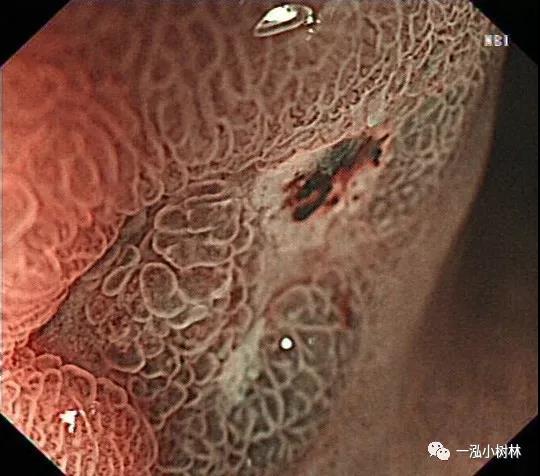

图2D 病灶A NBI+ME:病灶边界线清晰且不规则,表面构造呈绒毛状,腺管拉长、大小不等、形态不规则,部分MS不清楚,内镜诊断为0-Ⅱc型早期胃癌,未分化,黏膜内。